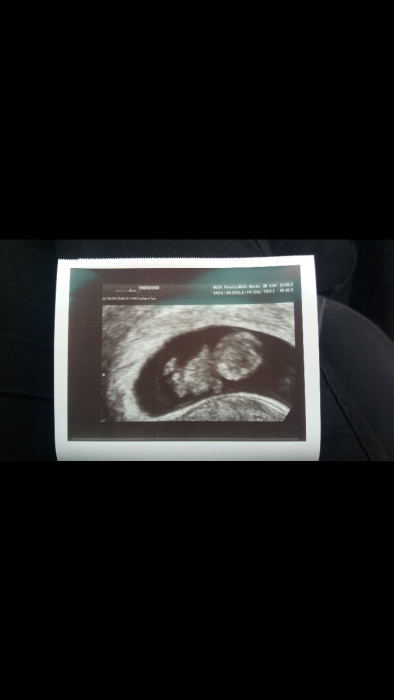

Ahoj holky. Taky se s svami podelim o radost. Jsem 9+2tt. Termin porodu byl 26.4., ale vcera se mi to posunulo uz na 29.4., tak to bude asi kvetnacek.Nevolnosti jsou na dennim poradku,do toho unava. Vcera jsem hyla na screeningu na krvi a pan doktor mi delal i utz. Mimco je cim dal vetsi..  jednu fotecku mam uz doma, ale neni tam nic videt. Po vcerejsu mam hned lepsi naladu, protoze si to uz zaciname s pritelem uvedomovat... mame tam uz krasne videt mimco  :-))  na genetiku jdu az za mesic, tak se modlim at vse dobre dopadne.  Tak vam poslu vcerejsi fotecku nasi rostouci fazolky :-)

[939179] jee fotka z UZ je kouzelna ja jsem dneska 10+3 ale takhle peknou fotku z uterni kontroly nemame